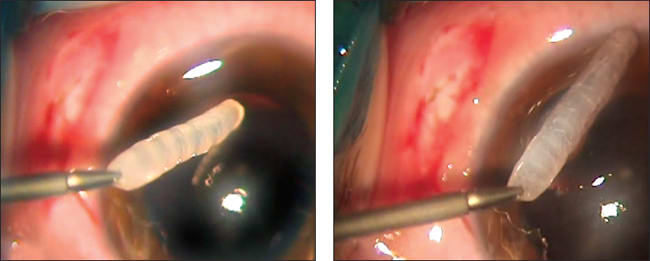

The first step in removing the larva was that it was fixed by the aspiration cannula and tucked up for expansion to a 2-mm sclerotomy (Figure 2). Next, we carefully removed the larva from the vitreous cavity with vitreal forceps, without damaging its integrity (Figure 3), and we placed it in physiological solution for further identification. As the final step, we performed endolaser coagulation around the retinal break and closure of the sclerotomy.

Figure 2. The larva was fixed by aspiration cannula.

Figure 3. The larva was removed from the vitreous cavity with vitreal forceps.